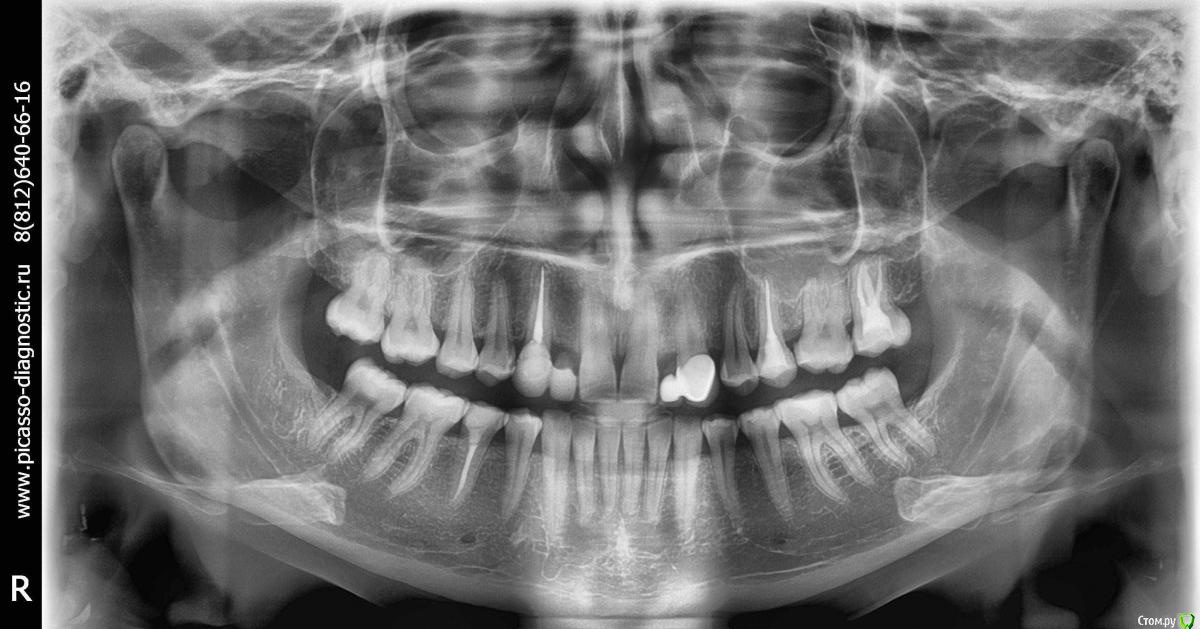

Здравствуйте, помогите определиться, пожалуйста. У меня нет верхних двоек. Стояли мосты с 15 лет. Сейчас один сняли, пока стоит временный. Я хотела сделать импланты, но врачи посмотрели КТ и сказали, что там очень мало места (3 и 5 мм), никак не воткнуть. Надо брекетами раздвигать место. Так вот я сходила к 3 ортодонтам и две сказали что брекеты нужны только на ВЧ, а одна что на обе. Я, конечно, хочу на одну - так проще и дешевле, а с деньгами у меня не густо. Но у меня зародилось сомнение - а, может, действительно надо на две делать? Что бы вы посоветовали?

потому что чтобы создать место под двойки надо как то создать это место. если просто толкнуть центральные резцы   (отодвинуть их вперед) будет щель, они будут торчать будет некрасиво.  толкнуть боковые зубы назад (одночелюстным лечением это невозможно, собьются все межчелюстные контакты)

отсюда вывод - надо менять всю форму и размер верхней челюсти, а потом под нее делать такую же  гармоничную нижнюю челюсть с хорошими межчелюстными контактами. поэтому две.